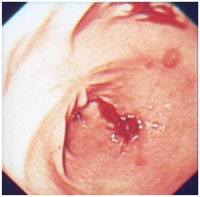

Un estudio que examina la forma más eficaz de suprimir el ácido gástrico

Un estudio que examina la forma más eficaz de suprimir el ácido gástrico

Este nuevo método podría eliminar la necesidad de realizar colonoscopías.